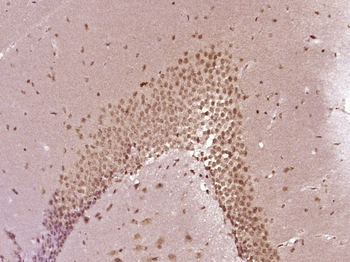

SF3B14 Rabbit Polyclonal Antibody

IF, IHC-Fr, IHC-P

应用稀释比例:IHC-P=1:100-500, IHC-F=1:100-500, IF=1:100-500